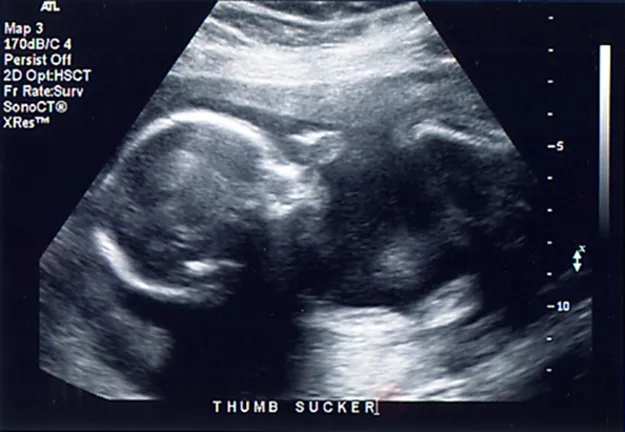

How much detail can ultrasound reveal? The image in Figure 17.43 is typical of low-cost systems, but that in Figure 17.44 shows the remarkable detail possible with more advanced systems, including 3D imaging. Ultrasound today is commonly used in prenatal care. Such imaging can be used to see if the fetus is developing at a normal rate, and help in the determination of serious problems early in the pregnancy. Ultrasound is also in wide use to image the chambers of the heart and the flow of blood within the beating heart, using the Doppler effect (echocardiology).

This is an image of a 3D ultrasound scan of the fetus showing an unborn baby sucking its thumb.

Figure 17.44 A 3D ultrasound image of a fetus. (credit: Jennie Cu, Wikimedia Commons)